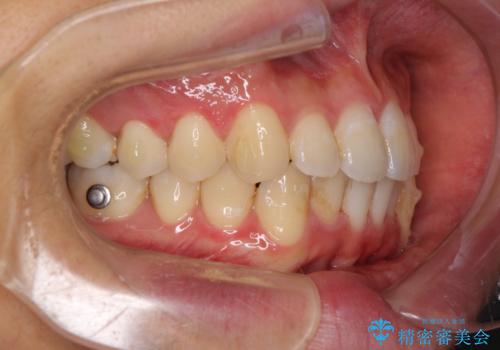

口が少し閉じにくい インビザラインによる非抜歯矯正

- インビザライン

- 口元の突出感を治したいとのことで来院された患者様です。

上下顎ともにIPR(歯と歯の間を削る)と歯列全体の拡大によって口元が引っ込むように設計し、インビザラインにより治療を行うこととしました。

抜歯をして口元を下げなければならないほど出っ歯ではなかったため、少しずつ治療ゴールを変更しながら仕上げていきました。

気になっていた前歯の飛び出した印象は、最終的にはスッキリと引っ込み、大変満足していただきました。